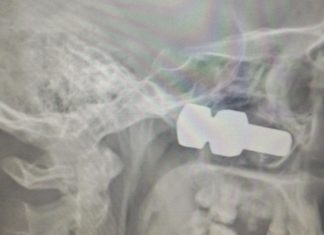

З-під колеса вантажівки вилетів болт, який потрапив в голову лесосибирцу

Якщо ви дивилися фільм "Пункт призначення", то після прочитання цього поста вам стане ще страшніше виходити на вулицю. Житель Лесосибирска чекав на трасі свого...